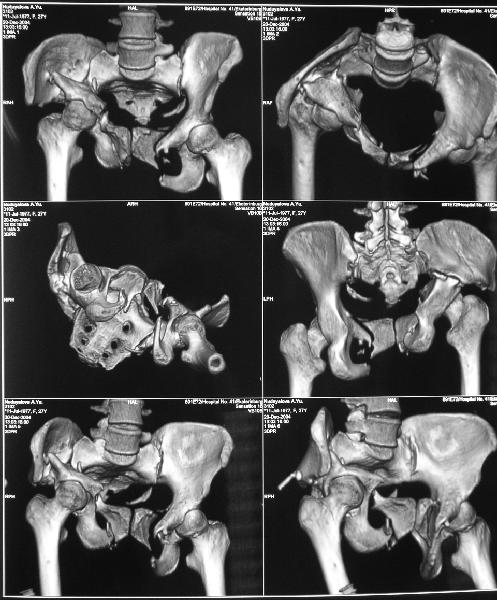

Снимки до лечения:

Картина на сегодня: